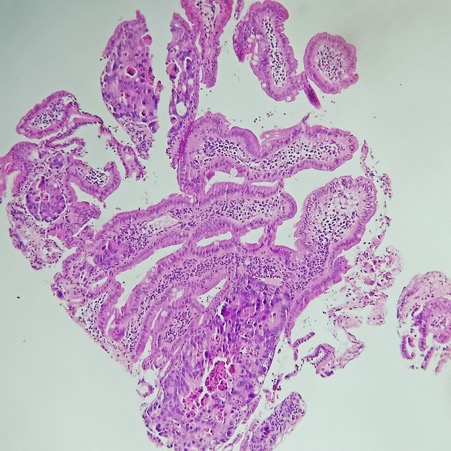

Gastric abnormalities show nonspecific gastrointestinal symptoms and similarly radiological findings. Intra and extra luminal gastric wall thickening are the most common finding in benign and malignant pathologic process. This aim of this case report was to describe several characteristics such as the location and size of the lesion, involvement of the gastric wall and surrounding structures, calcifications, and contrast enhancement pattern which can assist in radiological diagnosis. Several cases at our institution have similar gastrointestinal complaints, however, there were different lesions characteristic found in contrast enhanced abdominal CT scan. The first case 72-years-old man experienced hematemesis with radiologic finding diffuse gastric mucosal thickening as well as homogenous contrast enhancement but without calcification. The second case 37-years-old man complaint dizziness and melena with radiologic finding large tumor more than 10 cm in size, amorph calcification and heterogenous contrast enhancement. The last 60-years-old man case experienced melena and hematemesis, from abdominal CT scan showed irregular gastric mucosal thickening with heterogenous contrast enhancement and fat stranding around the lesion, without calcification. Methods used in these cases were contrast-enhanced abdominal CT scan, esophagogastroduodenoscopy (EGD), and biopsy in order to determine the diagnosis. Contrast-enhanced abdominal CT scan plays a vital role in describing the lesion characteristics which affects the determination of treatment options and future prognosis.